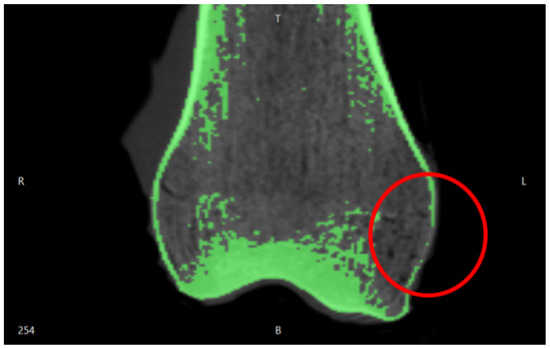

3.1. Imaging Acquisition and Mesh Processing